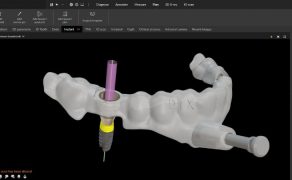

Metody zapobiegania złamaniom narzędzi w kanale korzeniowym

Title: How to prevent separation of endodontic

instruments in root canal

Złamane narzędzie kanałowe podczas wymagającego precyzji i czasochłonnego leczenia kanałowego jest jednym z wielu możliwych powikłań, które może mieć wpływ na rokowanie. Z badania przeprowadzanego w grupie 330 lekarzy stomatologów praktykujących w Wielkiej Brytanii wynika, że 317 (88,8%) spośród nich przynajmniej raz doświadczyło tego powikłania [1]. Odsetek złamań instrumentów waha się pomiędzy 0,7% a 7,4%, i częściej dotyczy narzędzi niklowo-tytanowych niż stalowych [2]. Wśród czynników, które mają wpływ na wystąpienie tego powikłania, wymienia się: doświadczenie lekarza, znajomość morfologii systemu kanałowego, technikę pracy instrumentami i procedurę sterylizacji [2-4]. Niepowodzeniem w leczeniu endodontycznym nie jest sam fakt pozostawienia narzędzia w kanale, lecz brak możliwości skutecznego oczyszczenia i opracowania obszarów położonych przywierzchołkowo.